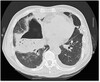

What pathology is seen here?

A

Cystic fibrosis

Lung looks scratchy